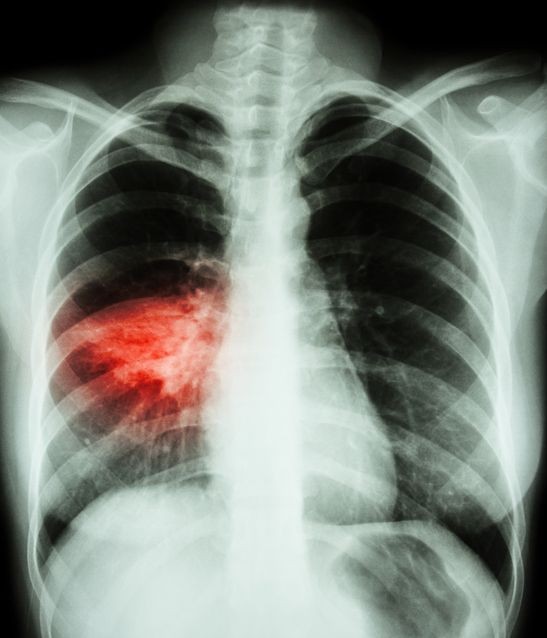

- Kupumua kwa shida.